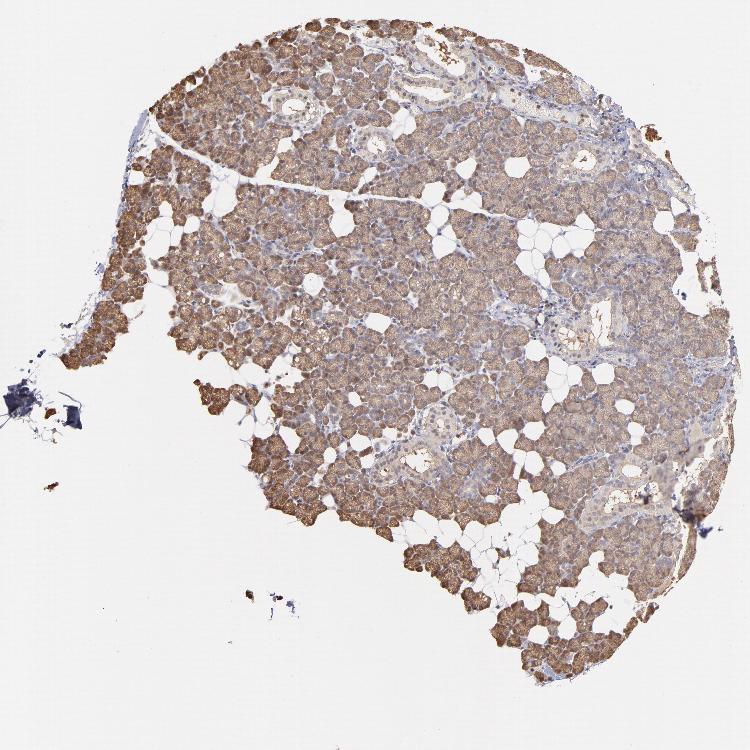

SALIVARY GLAND - Antibody stainingi

Antibody staining in the annotated cell types in the current human tissue is reported as not detected, low, medium, or high, based on conventional immunohistochemistry profiling in selected tissues. This score is based on the combination of the staining intensity and fraction of stained cells.

Each image is clickable and will lead to virtual microscopy that enables deeper exploration of all samples and also displays staining intensity scores, fraction scores and subcellular localization as well as patient and tissue information for each sample.

Antibody HPA051993Antibody CAB003835

Glandular cells MediumMedium